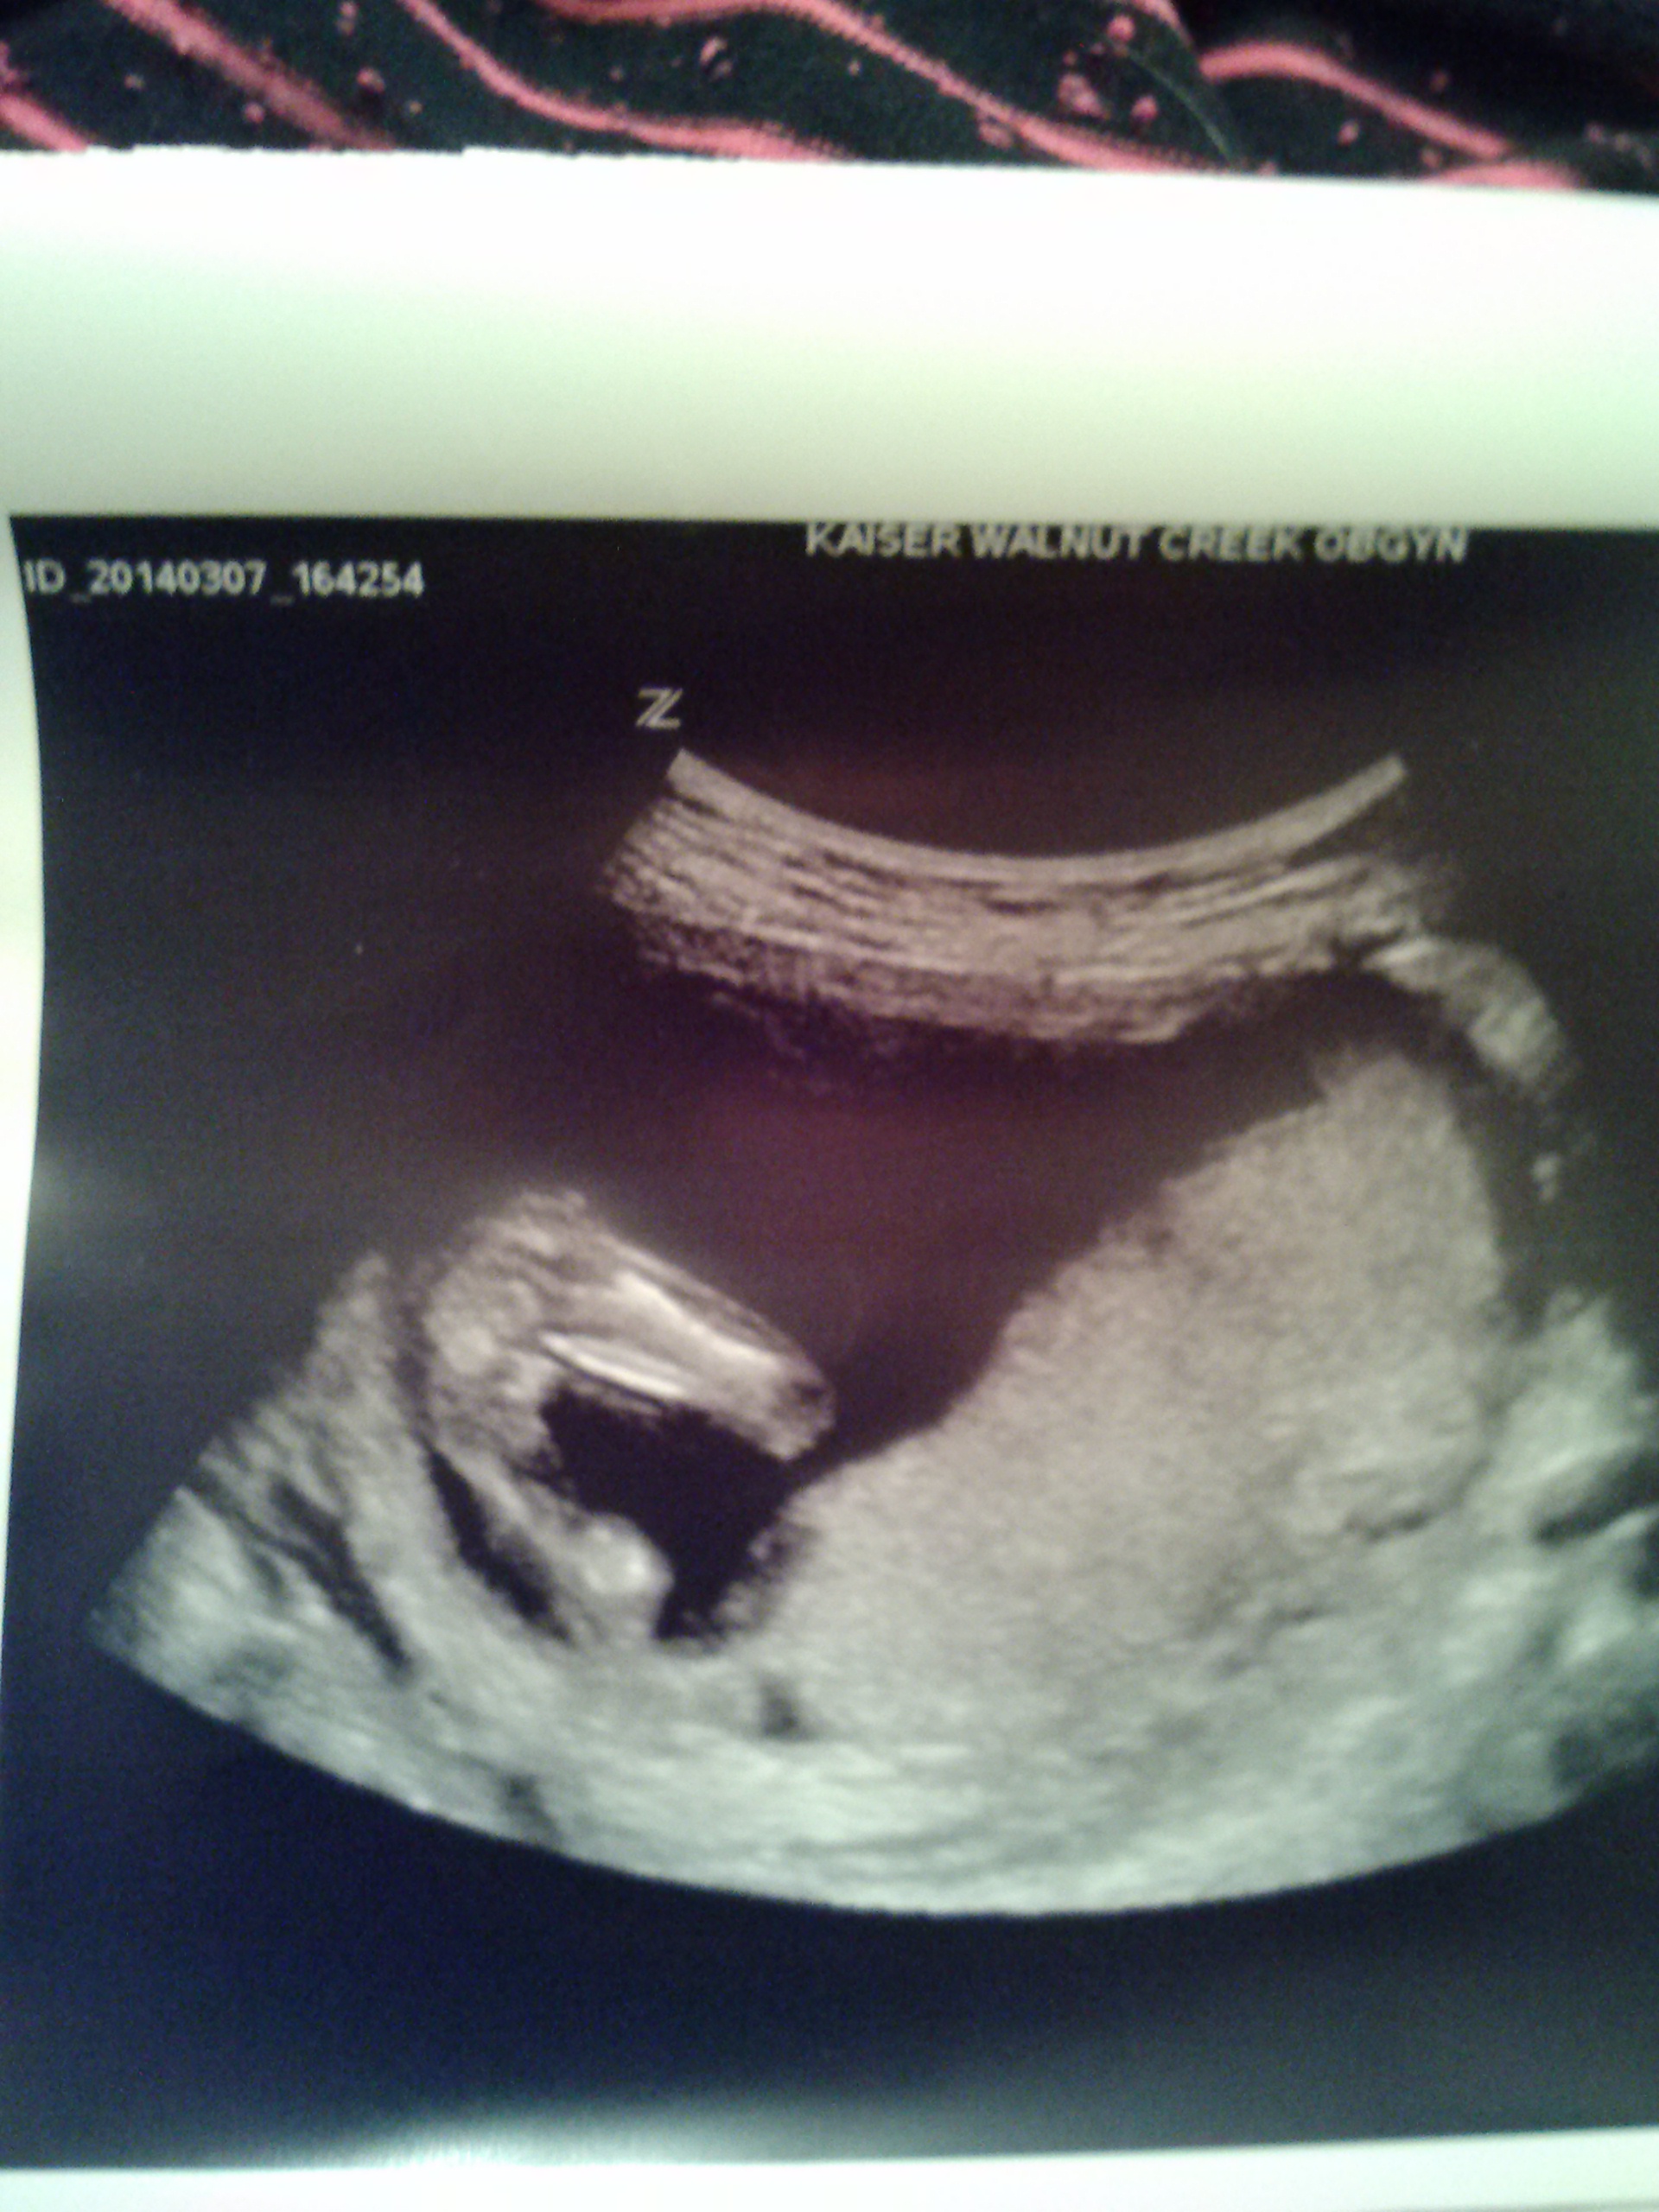

What about when you look at the potty shot....it was very early so maybe not reliable.....but in a close up i swear i see two round testicles or??? But i dont really see a weiner in between....the nub is early too so i am driving myself crazy with this! I cannot tell you how bad i want a boy......t

Your second shot is a very clear boy nub!

i think its a GIRL. Look at my potty shot at 12 weeks. VERY boyish looking.Attachment 18038